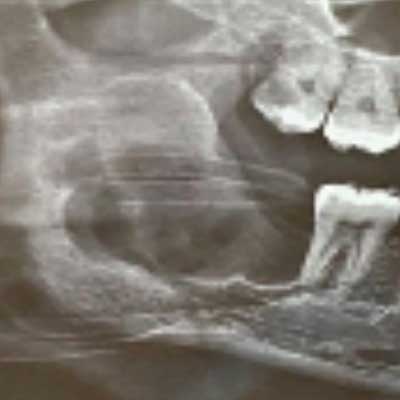

This is a representative case of an Odontogenic Keratocyst which was thankfully, caught early, during a routine dental xray (which is often the case)

Odontogenic Cyst 2

The entire cyst was removed in-toto using an intra-oral approachalong with the offending tooth. There was no external skin incision and the healing was uneventful.